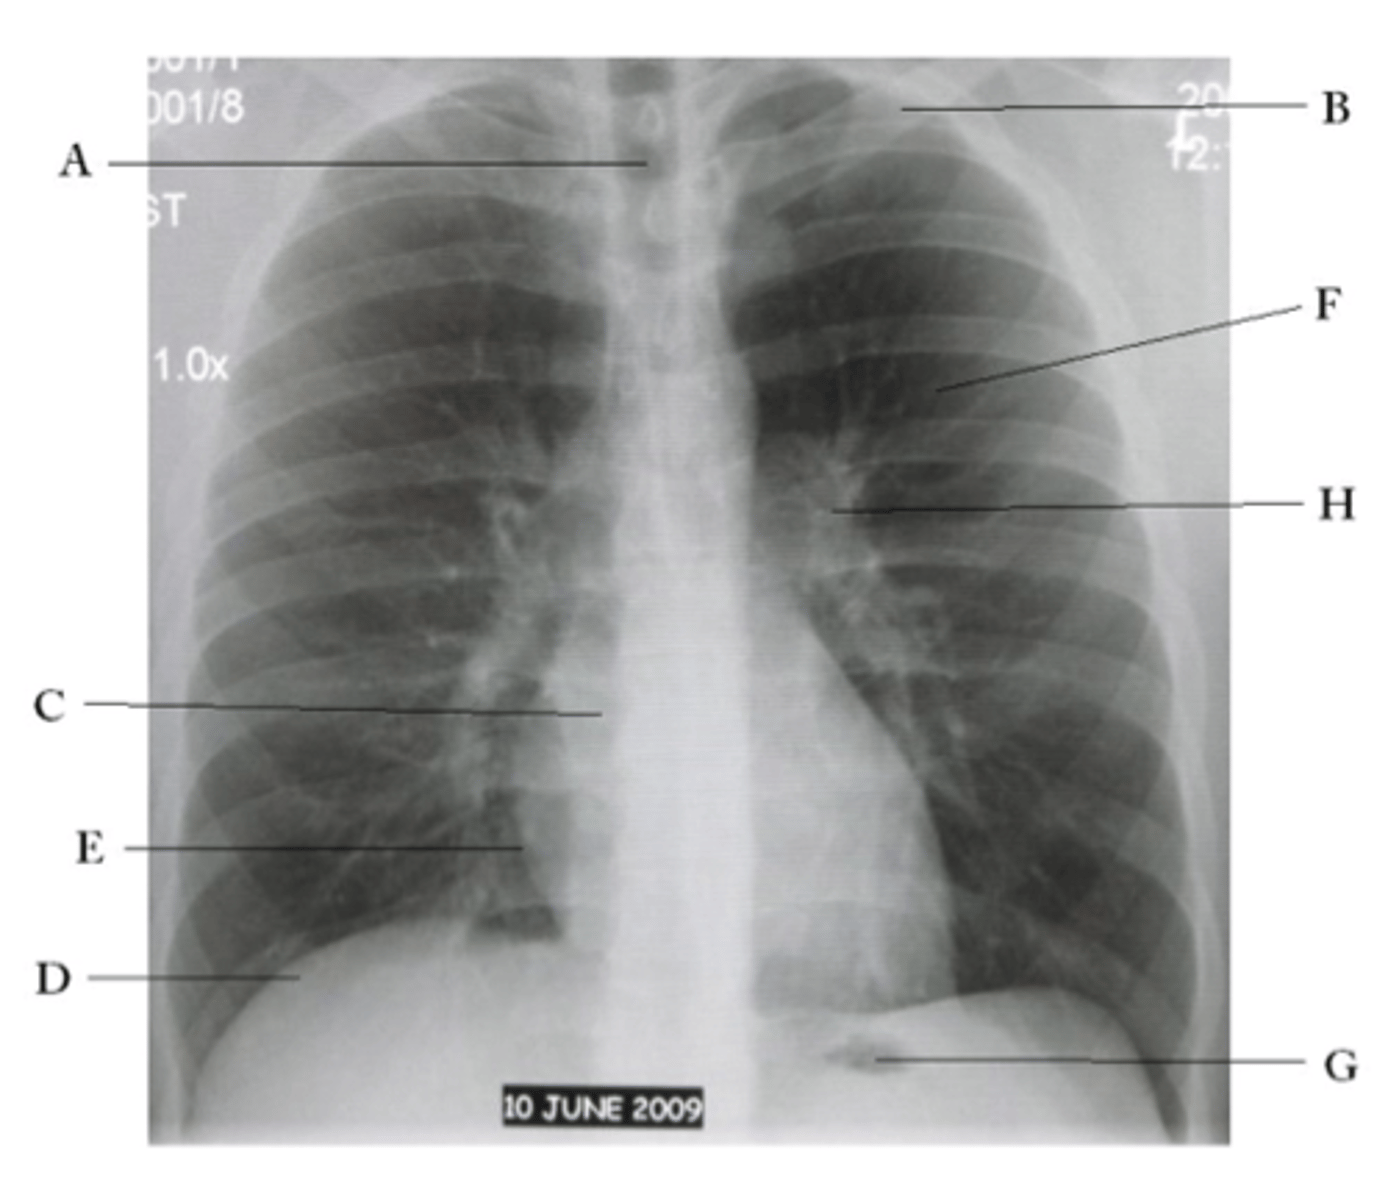

ID structures

oA - Trachea

oB - Clavicle

oC - Right Atrium

oD - Diaphragm

oE - Cardiophrenic angle (Costocardio)

oF - Left upper lobe

oG - Gastric Bubble

oH - Left Hilum

<p>oA - Trachea</p><p>oB - Clavicle</p><p>oC - Right Atrium</p><p>oD - Diaphragm</p><p>oE - Cardiophrenic angle (Costocardio)</p><p>oF - Left upper lobe</p><p>oG - Gastric Bubble</p><p>oH - Left Hilum</p>